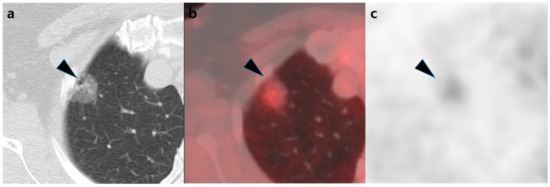

| Visual analysis of [18F]FDG PET/CT | 0.001 * | ||||

| Positive | 22 (88%) | 4 (44%) | 1 (17%) | 27 (68%) | |

| Semi-quantitative analysis of [18F]FDG PET/CT | |||||

| SUVmax | 1.3 (1.1–1.8) | 1.1 (0.7–1.8) | 0.6 (0.5–0.9) | 1.3 (0.8–1.8) | 0.033 * |

| SUVmaxTF | 2.6 (2.2–3.1) | 2.2 (1.9–2.9) | 1.6 (1.5–1.7) | 2.4 (1.9–3.0) | 0.018 * |